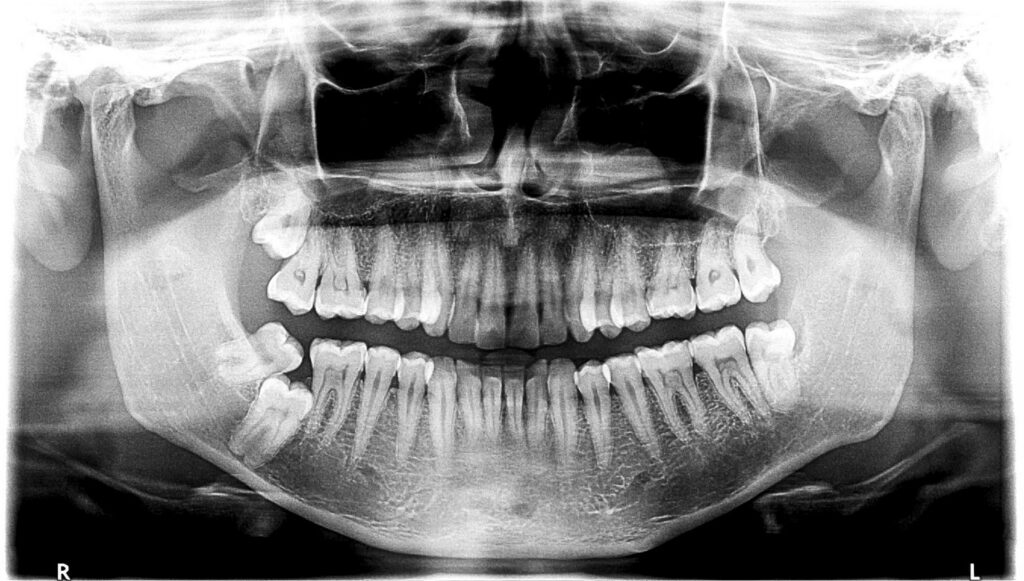

Cyfrowe technologie w diagnostyce stomatologicznej stomatologia cyfrowa zmieniają sposób, w jaki pacjenci są diagnozowani i leczeni. Dzięki nowoczesnym rozwiązaniom, takim jak tomografia komputerowa oraz diagnostyka 3D, lekarze mogą dokładniej ocenić stan zdrowia jamy ustnej. Innowacje te wpływają na jakość usług oraz wygodę osób korzystających z nich. Zastosowanie tych technologii pozwala na tworzenie spersonalizowanych planów terapeutycznych …